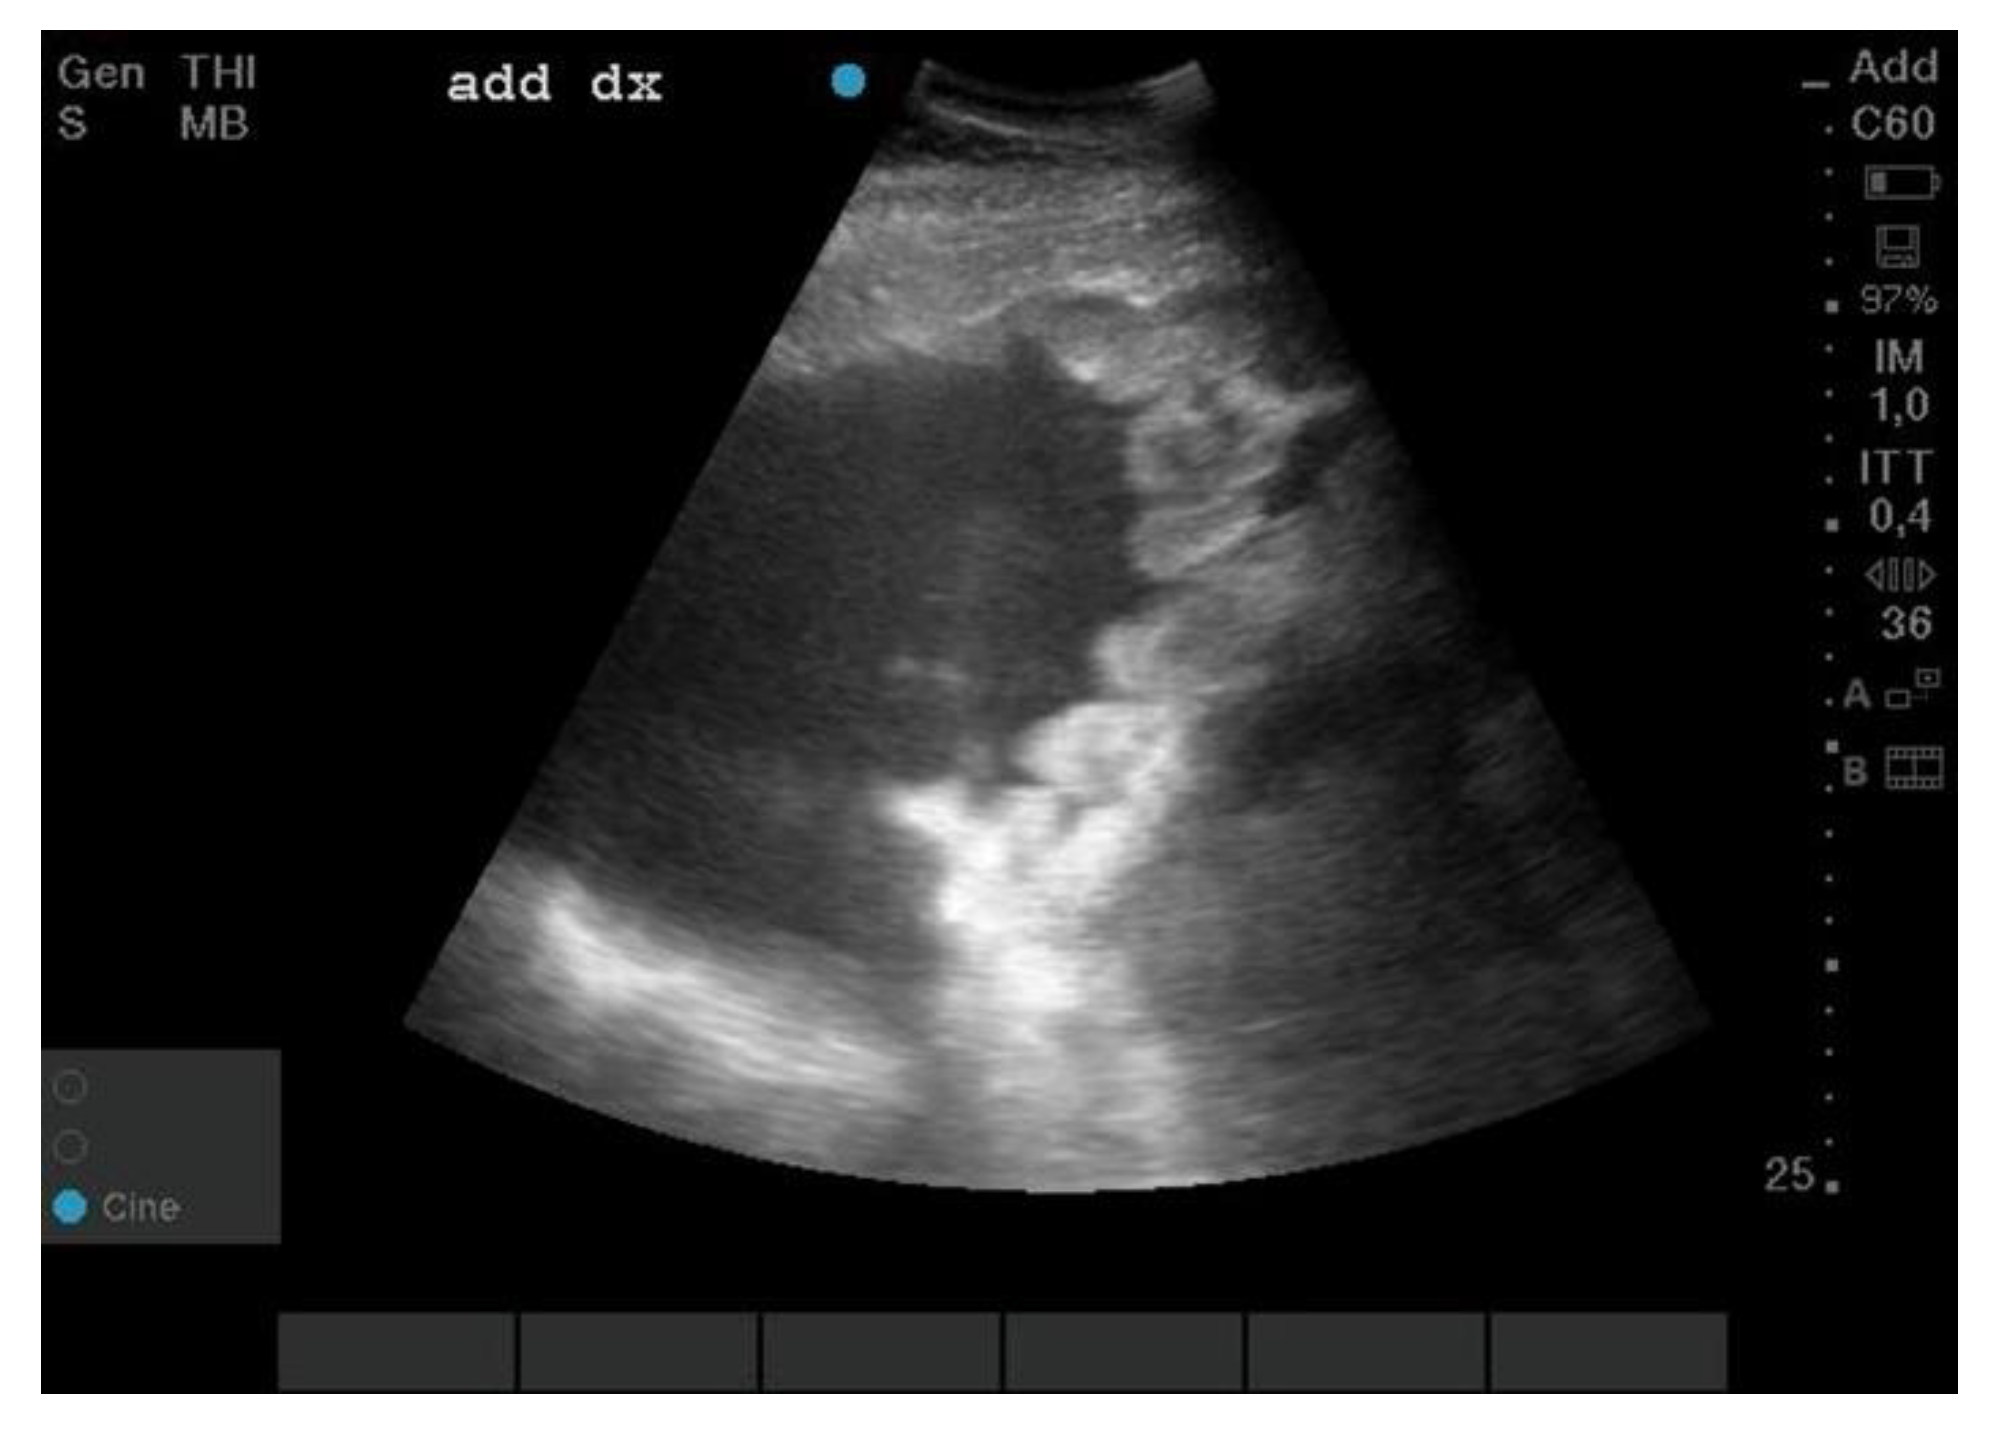

2.1. Clinical History

3.1. Necroscopic Examination